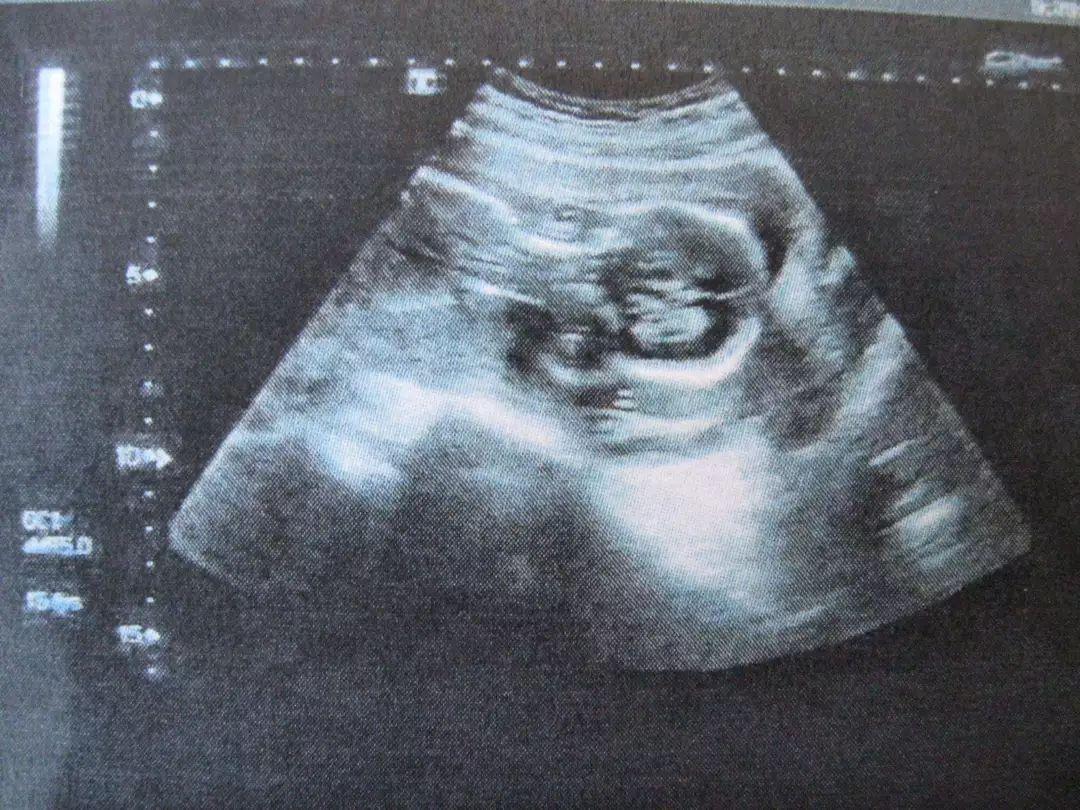

3、B超

超声波能发现肠反射的异常。